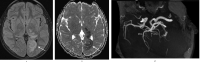

Arterial ischemic stroke is a rare but significant cause of neurological deficits in childhood. Even though there is a variety of risk factors, identifying the etiology can sometimes be a hard diagnostic challenge. Arteriopathies in general, and more specifically, arterial dissection is one of the uncommon pathologies that can cause incidents of pediatric stroke. We report a rare case of a young adolescent with posterior cerebral artery dissection after excessive consumption of caffeine, contained in energy drinks, only hours before the onset of neurological symptoms. A complete neuroimaging evaluation (MRI, intracranial US and digital subtraction angiography) at the admission and during the follow-ups supported the diagnosis of arterial dissection possibly caused by caffeine overconsumption.